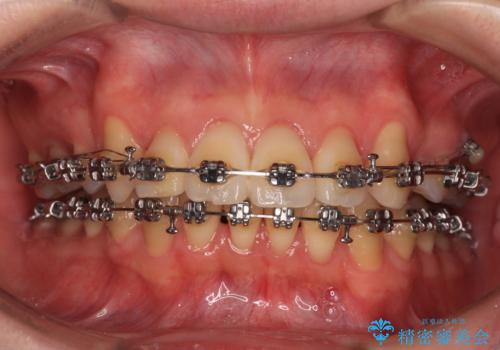

- 矯正装置

- メタルブラケット

- 2年11ヶ月

- 治療回数

- 30回以上

また、左右ともに上顎最後臼歯が頬側に転移していたため、補助装置を用いて舌側に移動をさせながら、上顎前歯を引っ込むように移動させることとしました。

口元の突出感を解消させるため上顎左右第一小臼歯2本を抜歯して、ワイヤー装置にて矯正治療を行うこととしました。